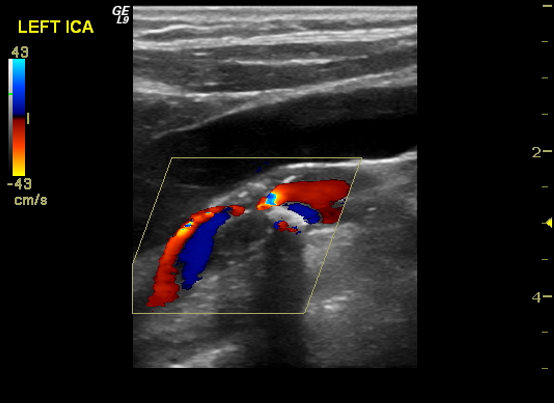

What vessel is being shown in this image?

Vertebral